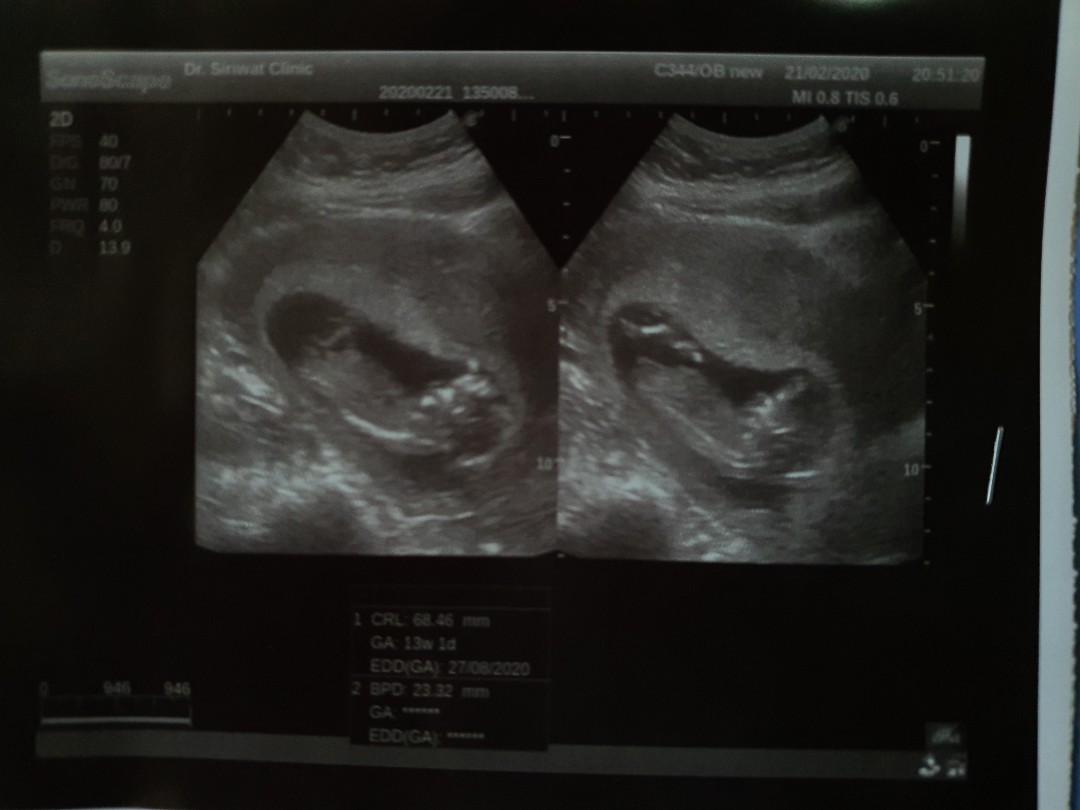

แม่ๆคนไหนมีภาพอัลตร้าซาวด์ประมาณ13วีคบ้างคะ ของเรา13วีค ภาพแบบนี้ค่ะ ดูไม่ออกเลย?

13w3d ตอนนี้21wเเร้วค่ะ